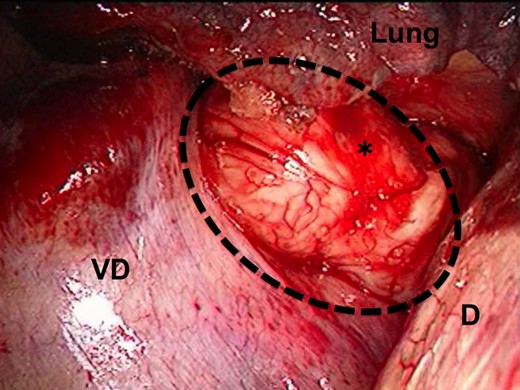

Thoracoscopic view of the tumor. The image shows bulging through the right thoracic cavity. The black dash line and asterisk indicate the GIST; D, the diaphragm; VD, the vertebral body.

A 62-year-old male was found to have a well-demarcated mass with a smooth surface at the right side of the lower esophagus by chest computed tomography (CT) upon medical check-up (Fig. 1). Routine laboratory data and the serum levels of tumor markers were within normal limits. Positron emission tomography (PET) revealed the accumulation of 18F-fluoro-2-deoxyglucose (FDG) at the tumor. The maximum standardized uptake value was 4.0, increasing to 4.8 in the late phase. Upper gastrointestinal endoscopy revealed no distinct mucosal abnormalities or no evidence of tumors. Endoscopic ultrasonography showed a mass ∼2 cm in diameter arising in the third layer 40 cm from the incisor teeth (Fig. 2a and b). These findings diagnosed the lesion as an esophageal submucosal tumor with suspecting an esophageal leiomyoma or GIST. Being under general endotracheal double-lumen anesthesia with split-lung ventilation, the patient was allowed to lie on the healthy side (left) and posture lateral decubitus. A 6-cm long access incision was made at the posterior axillary line in the 10th intercostal space. Two 10.5-mm ports were made at the seventh intercostal space in the anterior axillary line and other at the same intercostal space in the posterior axillary line. After no adhesion in the thoracic cavity was observed, the pulmonary ligament was dissected and the lower lobe of the right lung was moved anteriorly. A tumefactive lesion was found in the lower esophagus. An incision was made in the mediastinal pleura, and the mass was confirmed at the outer longitudinal muscle of the lower esophagus. The tumor was easily removed from the surrounding tissue by a tumor enucleation procedure. No esophageal mucosa was injured intraoperatively. The operation time was 118 min, and the blood loss was 11 g (Fig. 3). Macroscopic examination found that the removed white parenchymal mass was 29 × 20 × 14 mm in size. Histopathological examination showed that the specimens stained with hematoxylin and eosin-contained tumor cells, which had elongated oval nuclei and eosinophilic and spindle-like reticulum, were arranged in fascicles without mitosis. Immunohistochemical results were positive for c-KIT, S-100 protein, CD34 and vimentin, and the specimen was diagnosed as a low-risk GIST (Fig. 4a and b). The patient took an uneventful postoperative course, was allowed to remove the surgical drain after confirming the clinical status by esophagography on postoperative day 9, and discharged on postoperative day 13. At 6 years after surgery, the patient was found to be healthy without tumor recurrence.